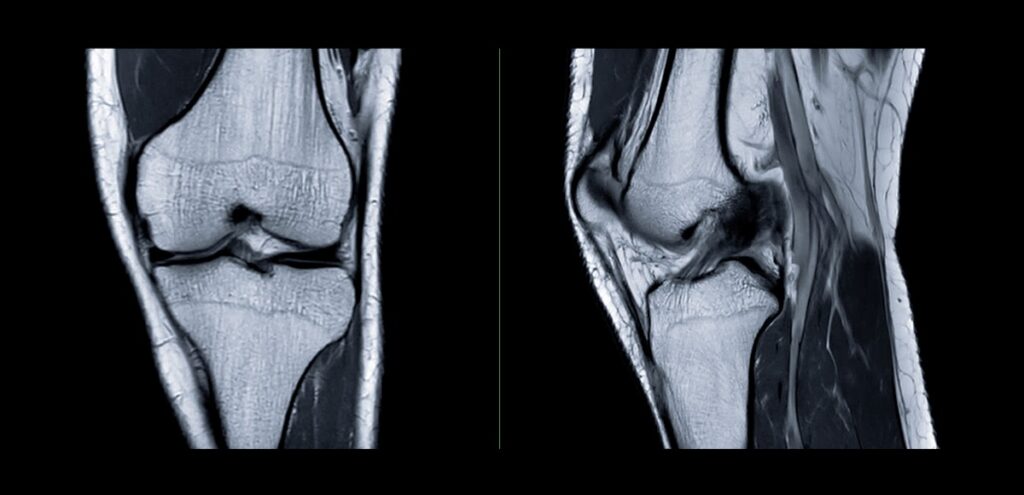

Quando dolore, gonfiore o limitazioni funzionali persistono, il medico può prescrivere una risonanza magnetica al ginocchio, un esame diagnostico di imaging avanzato che permette di visualizzare in modo dettagliato tutte le strutture articolari.